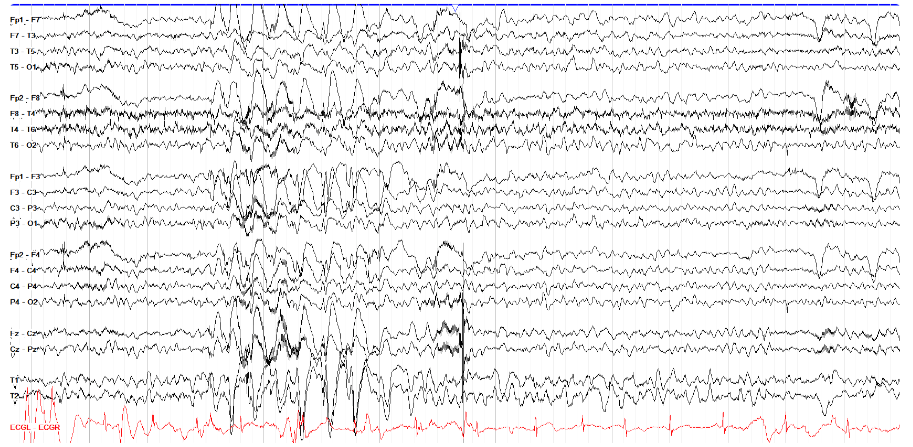

③ 胸部物理治疗伪影(Chest physiotherapy artifact)

在医院,特别容易发生在 ICU 中接受插管和镇静的患者中,因为它可能看起来像癫痫发作一样有节律,但通过观看视频(如果有)可以轻松区分这两者(即使没有敏锐的电生理技能)。

在脑电图上,它通常也与癫痫发作不同,因为它缺乏场或演变。胸部 PT 往往在后方更加突出,但根据患者的位置和 PT 的应用位置,情况可能会有很大差异。